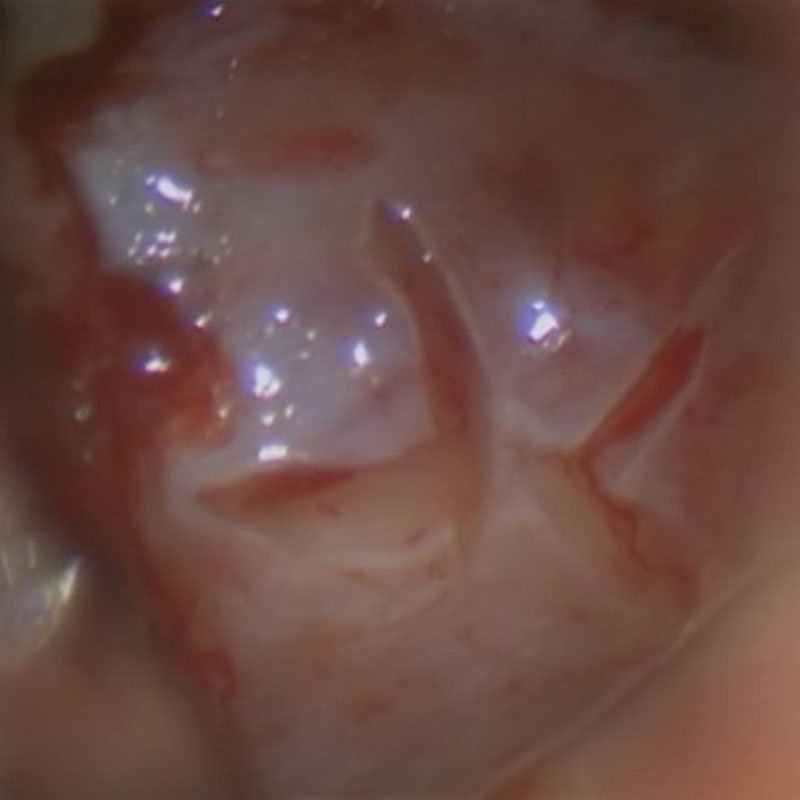

術中写真

摘出 前

摘出 中

摘出 後